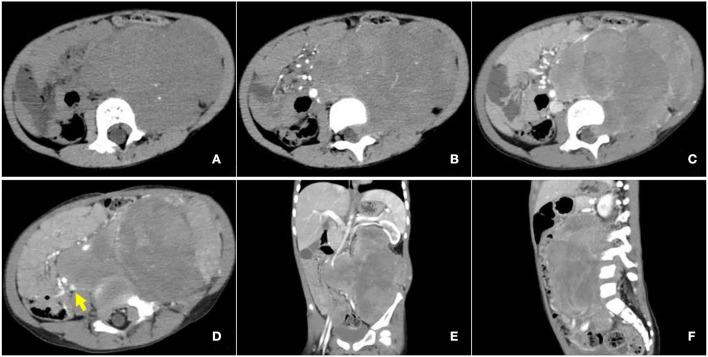

A 3-year-old female child was accidentally found with a large left upper abdominal mass for a day. CT examination indicated a huge soft tissue mass in the left retroperitoneum extending superiorly to the level of the left hilus renalis and inferiorly to the left acetabulum in the pelvic cavity, with intrusion into the lumbar foramens. F-FDG PET/CT found a mass in the left retroperitoneum from the level of T12 to the left acetabulum, with the maximum standardized uptake value (SUV) of about 7.0, and a CT value of about 39 HU, invading the left L3-5 intervertebral foramina and protruding into the spinal canal, with unclear boundary with the spinal cord. Retroperitoneal tumor resection and the repair operation of vascular exploration were performed. An ARMS was confirmed by postoperative biopsy, immunohistochemical staining, and genetic detection with the rupture of the fork head in rhabdomyosarcoma (FKHR). The patient received chemotherapy and was in a good condition with no recurrence and obvious complications.

一名3岁女童偶然发现左上腹有一巨大肿块1天。CT检查显示左腹膜后有一巨大软组织肿块,向上延伸至左肾门水平,向下延伸至盆腔内左髋臼,侵入腰椎间孔。F-FDG PET/CT发现左腹膜后从T12水平至左髋臼有一肿块,最大标准化摄取值(SUV)约为7.0,CT值约为39 HU,侵犯左L3-5椎间孔并突入椎管,与脊髓边界不清。行腹膜后肿瘤切除术及血管探查修复手术。术后活检、免疫组化染色及基因检测证实为ARMS,伴有横纹肌肉瘤叉头蛋白(FKHR)断裂。患者接受化疗,目前情况良好,无复发及明显并发症。